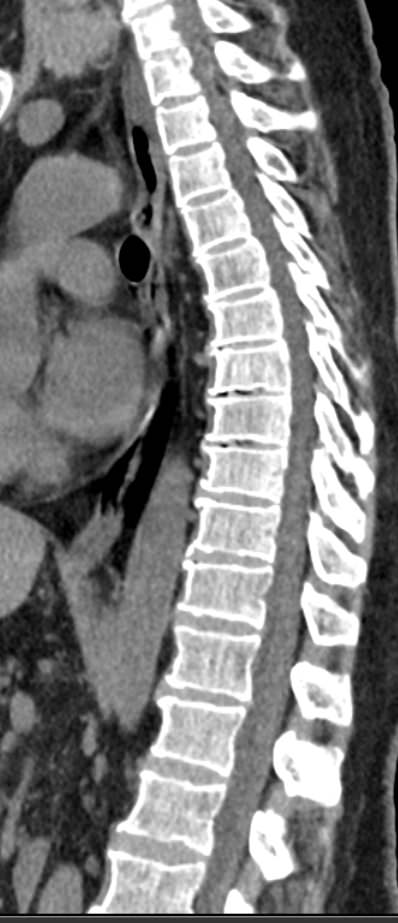

Мультиспиральная компьютерная томография является одним из наиболее информативных методов диагностики дегенеративно-дистрофических заболеваний, травматических, воспалительных изменений, а также опухолевых процессов позвоночника. Методика предусматривает использование рентгеновского излучения для получения детализированных снимков костных структур позвоночника, межпозвонковых суставов и межпозвоночных дисков.

При подозрении на распространенный процесс с поражением различных уровней позвоночного столба показано проведение мультиспиральной КТ трех отделов позвоночника.

В клинике «Доступная медицина» установлены современные мультиспиральные компьютерные томографы экспертного класса TOSHIBA AQUILION в различных модификациях (64-срезовый и 128-срезовый), на которых выполняются комплексные обследования позвоночника, включая одномоментное исследование несколько отделов. Аппараты производят сканирование с помощью рентгеновских лучей, делая тончайшие срезы с шагом от 0,5 мм, затем с помощью компьютерных программ полученные данные преобразуются в изображения трехмерного формата, что обеспечивает точность и достоверность диагностики.

Что покажет КТ трех отделов позвоночника

С помощью мультиспиральной КТ можно диагностировать:

- патологические изгибы позвоночника, сколиоз, усиленный или выпрямленный лордоз как нарушение статической функции позвоночника;